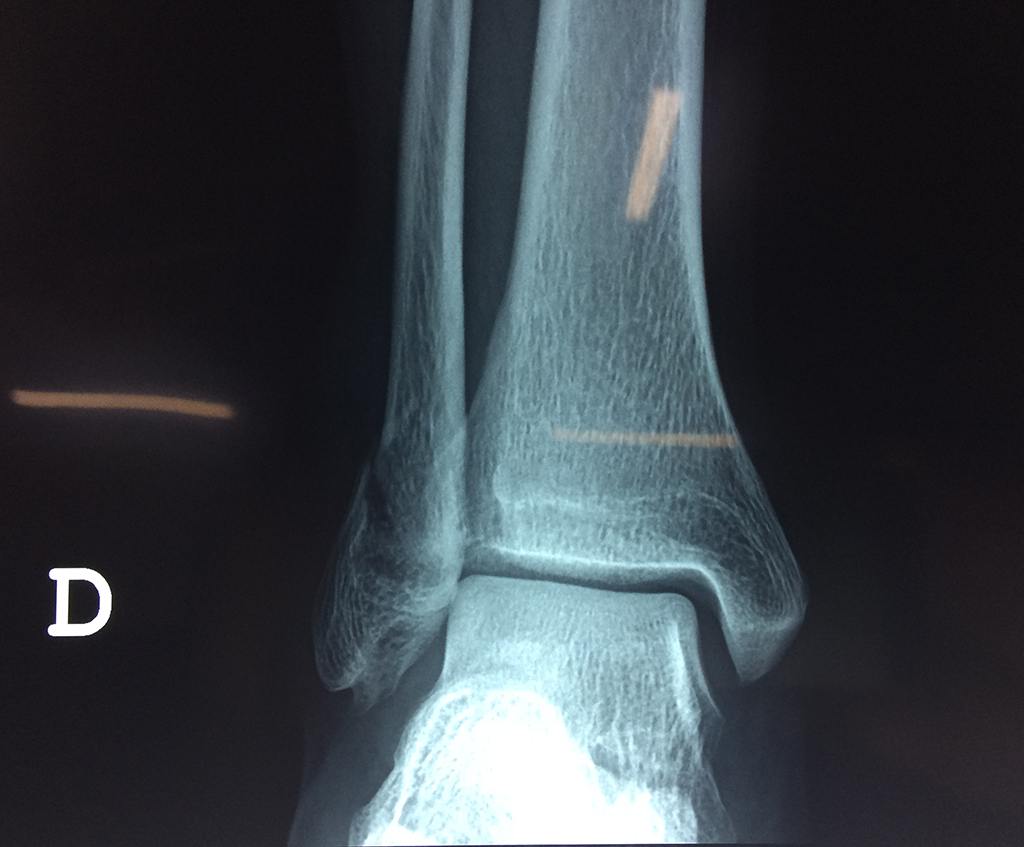

Una fractura de tobillo es la rotura de uno o más de los huesos del tobillo. Estas fracturas pueden ser:

Algunas fracturas de tobillo pueden requerir cirugía si:

- Los extremos de los huesos están desalineados entre sí (desplazados).

- La fractura se extiende hasta la articulación del tobillo (fractura intra-articular).

Cuando se necesita cirugía, es probable que esta implique el uso de clavijas de metal, tornillos o placas para sostener los huesos en su lugar mientras la fractura se consolida. Los elementos de soporte pueden ser temporales o permanentes.